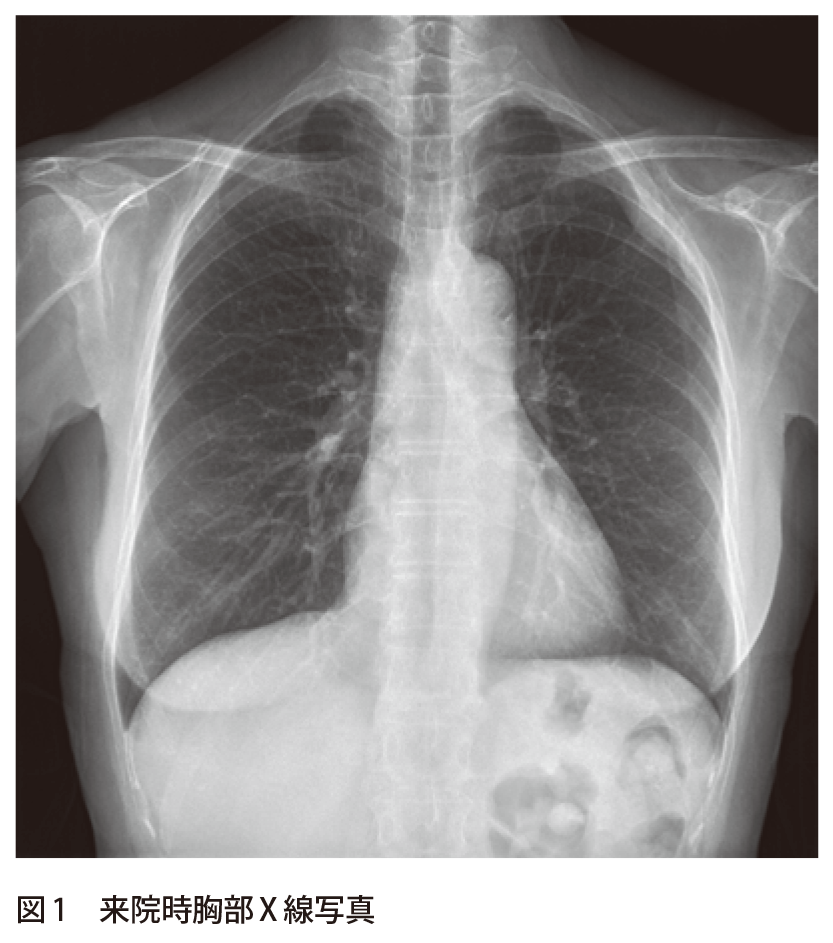

解答 解説 胸膜炎疑いで紹介受診した60歳代女性 実践 画像診断q A 羊土社 レジデントノート 羊土社

解答 解説 健診にて胸部異常陰影を指摘された60歳代女性 実践 画像診断q A 羊土社 レジデントノート 羊土社